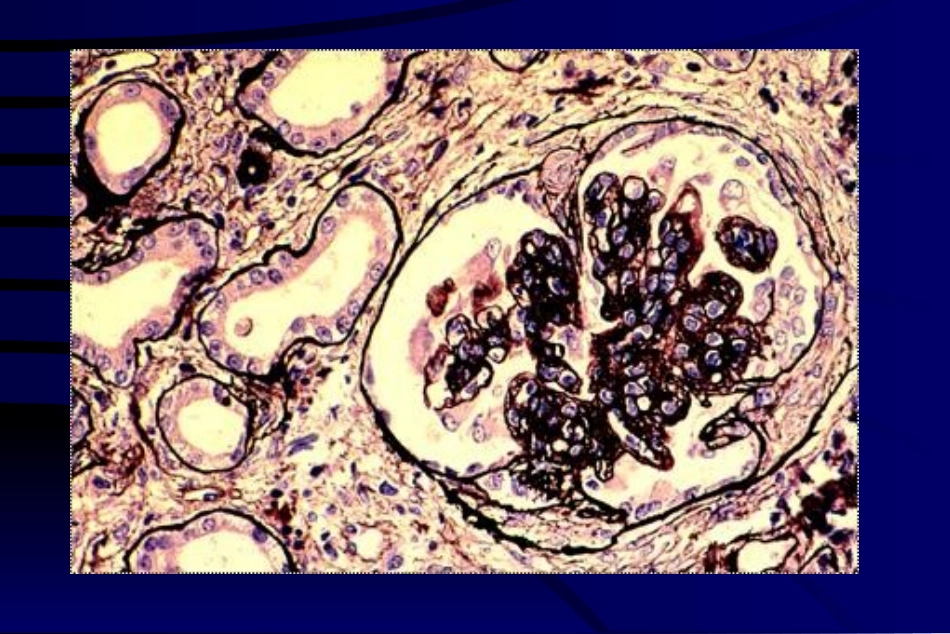

继发性肾小球肾炎IgAIgA肾病或肾小球肾炎肾病或肾小球肾炎•病因发病机制:粘膜损伤→IgA形成→含IgA的大分子的免疫复合物沉积于肾小球•病变特点:–免疫病理:以IgA为主的免疫球蛋白和C3沉积于系膜区。–光学显微镜:局灶性或弥漫性的,除膜性肾小球肾炎以外的各型肾小球肾炎。•临床表现:可出现血管炎和紫癜及各型肾炎综合征。狼疮性肾炎狼疮性肾炎•病因发病机制:自身免疫性疾病。含抗核抗体、抗细胞浆抗体、抗球蛋白抗体、抗细胞膜抗体等多种免疫复合物,沉积于肾小球•病变特点:–免疫病理:含IgG、IgA、IgM、C3、C4、C1q的多种免疫复合物,沉积于肾小球的各个部位。–光学显微镜:局灶性或弥漫性的,各型肾小球肾炎。•临床表现:可出现全身(心、肝、脑、关节、皮肤等)多系统病变及各型肾炎综合征。各型GN的演变关系毛细血管内增生性GN膜增生性GN局灶性GN系膜增生性GN微小病变性GN正正常常肾肾小小球球新月体性新月体性GNGN硬化性硬化性GNGNFSGS膜性GNKEYWORDKEYWORD•glomerulinephritis,EndocapillaryproliferativeGN,MembranousGN,•MesangioproliferativeGN,MembranoproliferativeGN,CrescenticGN,•MinimalchangeGN,FocalGN,SclerosingGN三、急性肾小管坏死(acutetubularnecrosis)由于休克或中毒导致的肾小管上皮细胞坏死,主要侵犯各段肾小管,主要临床表现为少尿、无尿和肾功能衰竭。概念概念::病因发病机制:休克,血压降低,肾缺血,肾小管缺血性坏死;毒性物质在肾小管浓缩,直接伤害肾小管上皮细胞。病理变化:肾小管上皮凝固性坏死,细胞碎片堵塞管腔,肾间质水肿;后期;肾小管上皮再生。肾小球缺血肾小球滤过率肾小管上皮坏死细胞碎片堵塞尿液返流肾间质水肿少尿或无尿后期,再生的肾小管上皮功能不全多尿和等比重尿休克或中毒肾缺血临床病理联系:CONCLUSION•Acutetubularnecrosis:tubularepithelialcellsshowdiffusecoagulationnecrosis,causedbyrenalischemiaorpoisoning,oftenoccuracuterenalfailure.•KEYWORD:Acutetubularnecrosis四、四、肾盂肾炎肾盂肾炎(pyelonephritis)(pyelonephritis)病原体感染直接引起的化脓性炎病原体感染直接引起的化脓性炎,,主要侵主要侵犯肾盂粘膜和肾间质犯肾盂粘膜和肾间质,,主要临床症状有急性感主要临床症状有急性感染的全身症状、血尿、白细胞尿或脓尿、下尿染的全身症状、血尿、白细胞尿或脓尿、下尿路刺激征。路刺激征。概念概念::病原体:大肠杆菌、链球菌、葡萄球菌、绿脓杆菌、霉菌等感染途径:上行性(大肠杆菌为主);血源性(少见,烈性化脓菌为主)诱发因素:下尿路梗阻;重病体弱,长期卧床患者病因发病机制病因发病机制::•急性肾盂肾炎急性肾盂肾炎::脓性卡它性炎脓性卡它性炎;;肾的蜂窝织炎肾的蜂窝织炎;;肾脓肾脓肿上行性感染者肿上行性感染者,,近肾盂处严重近肾盂处严重,,肾皮质轻肾皮质轻,,单肾发单肾发病或双肾分布不均血源性感染者病或双肾分布不均血源性感染者,,双肾弥散分布双肾弥散分布,,以以肾小球为中心形成小脓肿。肾小球为中心形成小脓肿。•慢性肾盂肾炎;淋巴和单核细胞浸润;肉芽组织形成慢性肾盂肾炎;淋巴和单核细胞浸润;肉芽组织形成,,结缔组织增生结缔组织增生;;厚壁脓肿厚壁脓肿;;肾盂变形肾盂变形;;瘢痕肾形成。瘢痕肾形成。病理变化:机体对微生物感染的全身反应机体对微生物感染的全身反应;;病变病变波及血管导致血尿波及血管导致血尿;;间质化脓性病变的细间质化脓性病变的细胞成分入尿导致尿异常胞成分入尿导致尿异常;;下尿路刺激征下尿路刺激征((尿频、尿急、尿疼尿频、尿急、尿疼))多见于上行感染者。多见于上行感染者。临床病理联系临床病理联系::CONCLUSION•Pyelonephritis:isasuppurativeinflammation,iscausedbyinfectionofsuppurativebacterium.Thepelvis,interstitiumandtubulesismajorinjurysite.Morphology:focalsuppurativeinflammation(phlegmonousinflammationorabscesses).Itsclinicalmanifestationsinclude:fever,malaise,flankpain,dysuria,frequencyandurgency,pyuriaandwhitecellcasts.五、五、过敏性间质性肾炎过敏性间质性肾炎(al...